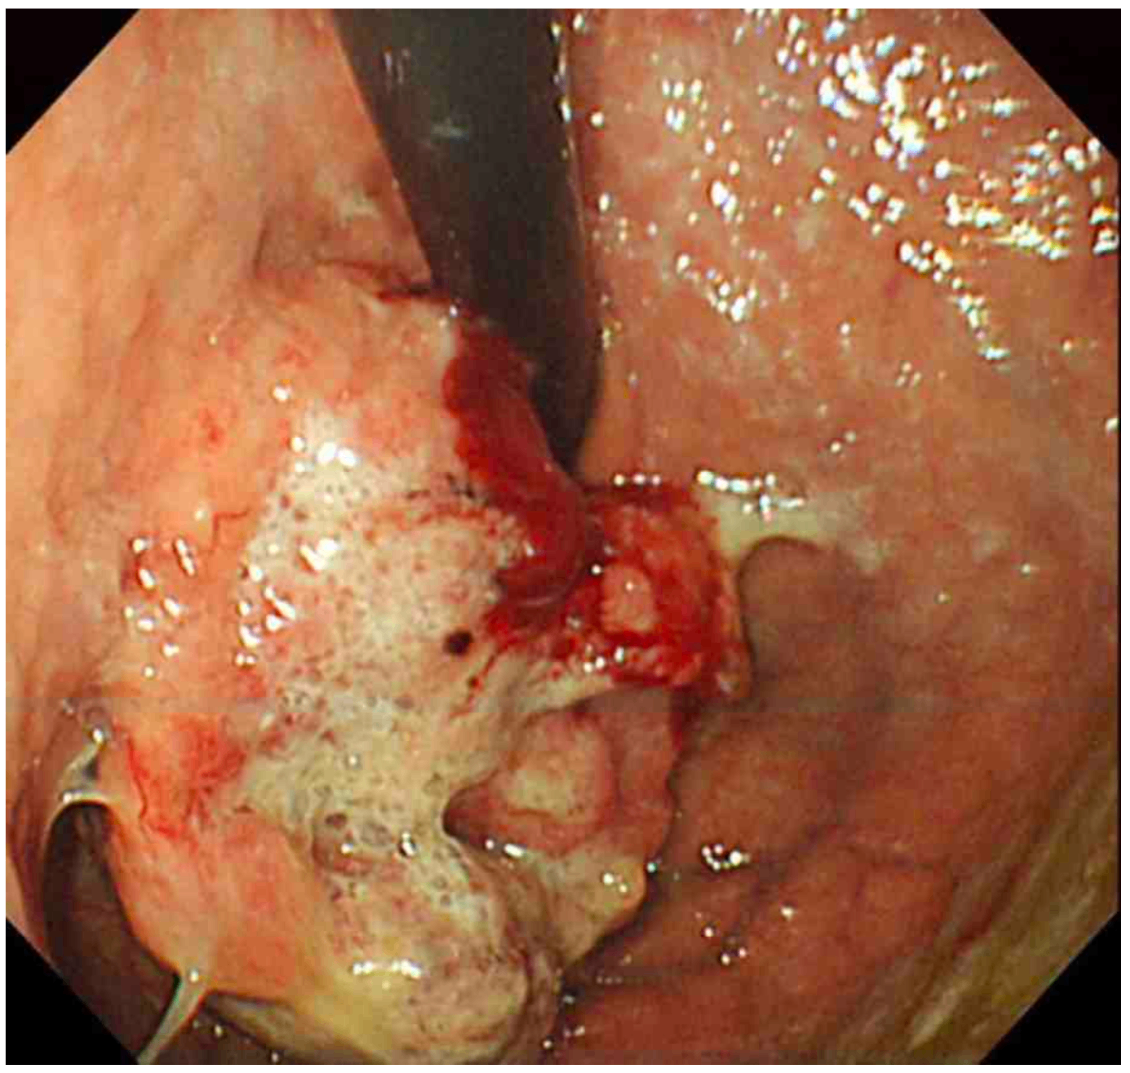

EGD: Gastric mass with bleeding, probably malignant

• 현재 V/S stable하며 복부 압통 또한 없으므로 원인 확인을 위해 EGD를 시행하였다. EGD상 출혈이 동반된 mass가 내강으로 돌출되어 있음이 확인되는데, 육안적으로 볼 때 위암이 강력히 의심된다.